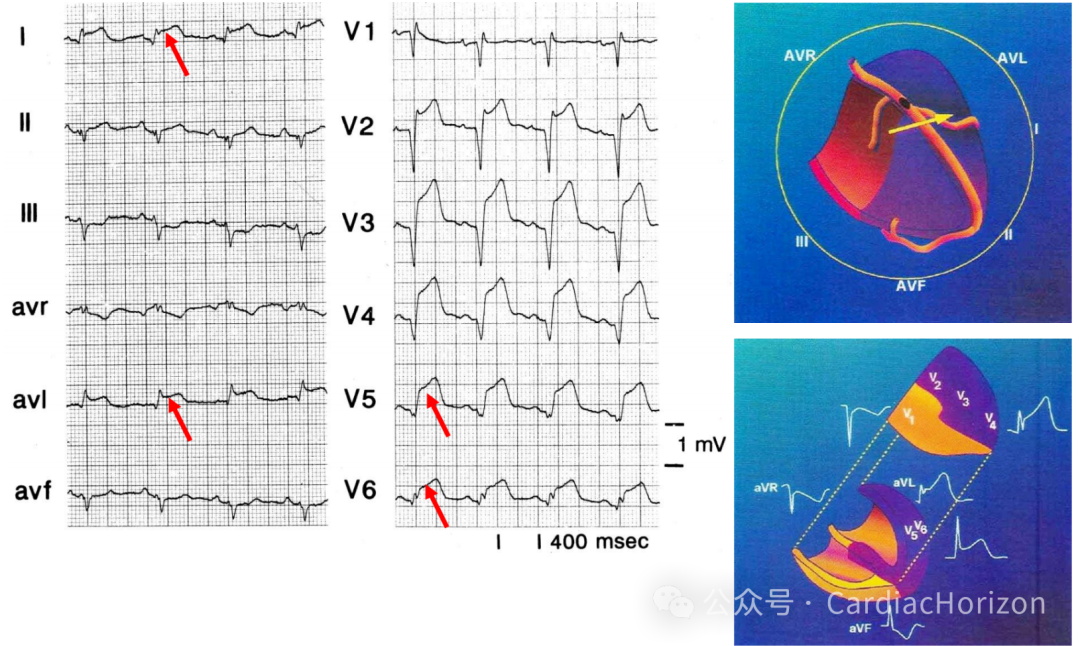

梗死相关血管可以为RCA或LCX,RCA 闭塞占 80%~90%, 约18%的下壁心梗由优势型LCX闭塞引起,极少数为左前降支病变引起

鉴别的点在于右冠还是回旋支闭塞,主要看II导联和III导联ST抬高幅度。

RCA闭塞 缺血向量指向右下,III导联ST抬高>II导联,I导联ST压低;

LCX闭塞 缺血向量指向左下,II导联ST抬高>III导联,I导联ST位于等电位线或抬高;

左侧导联(I、aVL、V5、V6)导联中≥1个出现ST段抬高提示侧壁MI,高度提示LCX闭塞;

STII抬高 >STIII抬高 或 I 导联的 ST 段无变化是 LCX 阻塞的标准。当 I 和 AVL 导联 ST 段抬高伴有 V2 导联 ST 段下移时, 则提示第一钝缘支闭塞 。V3 导联 ST 段压低幅度与 II 导联 ST 段抬高幅度的比值 (STV3↓/STIII↑)>1.2 时,罪犯血管多为左 LCX。

急性后壁心梗罪犯血管多为回旋支,V7~V9导联ST段抬高,无aVL导联ST段压低,对LCX闭塞具有高度敏感性与特异性;